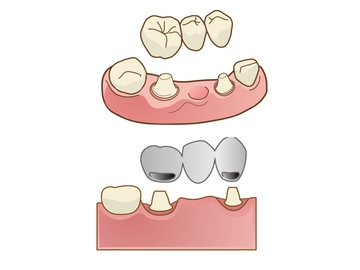

オーラルエステです今日は被せ物(補綴物)の種類を紹介

インレー

クラウン

ブリッジ